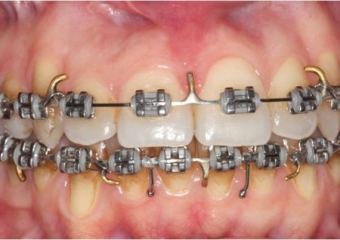

Mordida inicial

Mordida após a cirurgia